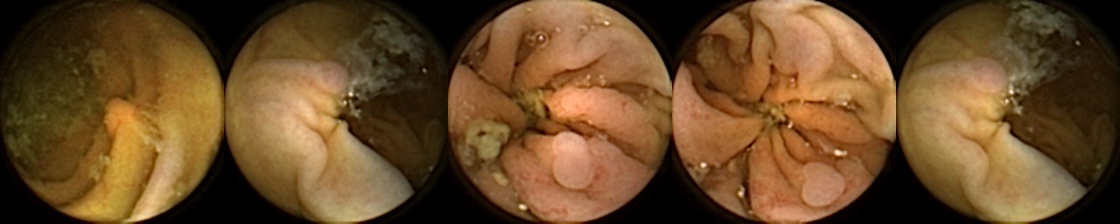

Figure 3 shows classification output examples for the MIV model using the pretrained ConvNext. Note that the model has a test accuracy of 83.66% for DBA L2 with 2 heads. In each row, the leftmost image is the query and the four images to the right of each query are the target images. The True Positive (left-top) and True Negative (bottom-right) examples outline the cases when the model is able to successfully distinguishes images containing unique polyps from those with dissimilar polyps. The False Negative (top-right) and False Positive (bottom-left) examples show the cases where the model fails to correctly distinguish images of unique polyps and images of dissimilar polyps. Further, we can note from the differences in the examples of True Positives and False Negatives that when the query image and the target set instances differ from each other in some ways, then the model can misclassify images. These differences could be attributed to different views due to the dynamics of the camera inside the colon, different views from two camera heads of the capsule, or presence of artifacts such as bubbles, debris, and small bowel secretions.

On the other hand, when we look at the examples of False Positives (Pred = true, Label = false) in Figure 3, we can note that if images in the target match the query in ways such as texture, color, illumination conditions, presence of artifacts, then this may lead to misidentification of the query as belonging to the targets. For True Negative (Pred = false, Label = false) examples, we can see that presence of significant differences between the query and the targets leads to correct identification of the image sets as different.

True Positive False Negative

False Positive True Negative

Figure 3: True Positives (Pred = true, Label = true), False Negatives (Pred = false, Label = true), False Positives (Pred = true, Label = false), True Negatives (Pred = false, Label = false) for the DBA L2(h=2) model using the pretrained ConvNeXt. In each row, the leftmost image is the query and the 4 images to the right of each query are the target images.